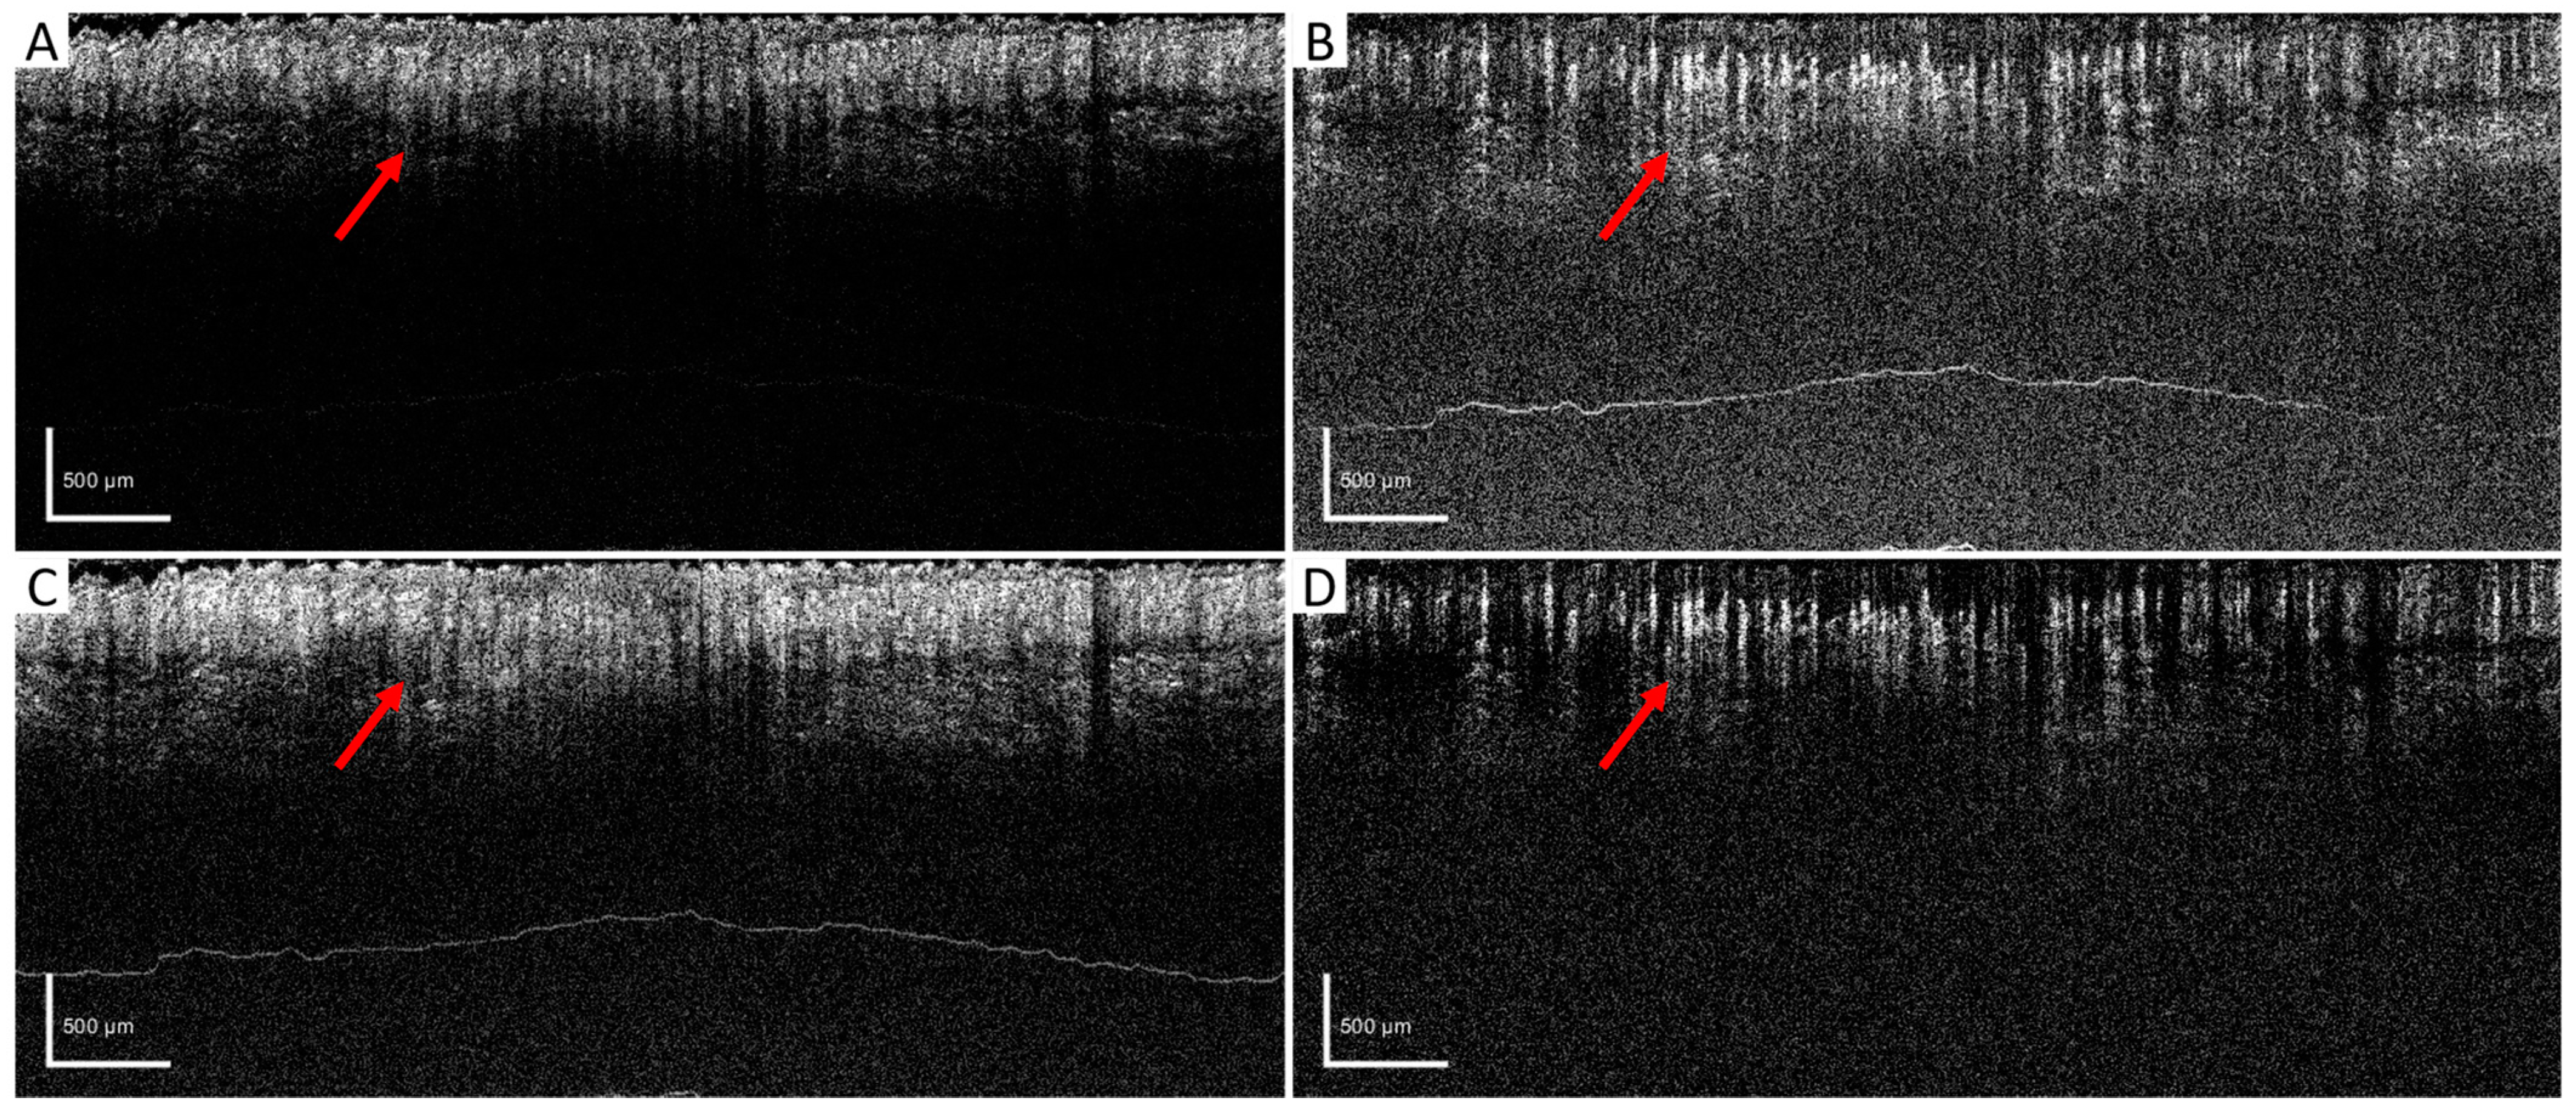

After setting the optimized window size for the wED algorithm, several other algorithms, aED [11,12], bED [12], and SV [7] were used to evaluate the performance of wED. In Figure 4, the same B-frame was processed with SV, aED, bED, and wED, which were shown in (A), (B), (C), and (D), respectively. Since only aED and wED could resolve blood flow signals, the background noise intensities of aED and wED results in Figure 4 were calculated by averaging the intensity within the regions that contained no OCTA signals (deep regions). The wED result had a noise intensity of 0.259, while the aED contributed to a noise intensity of 0.316.

Figure 4. B-scan comparison. The same B-scan frame with 4 repeating times was processed by (A) SV, (B) aED, (C) bED, and (D) wED, respectively. Regions that have differences in OCTA reconstruction were pointed out with red arrows. SV: Speckle Variance; aED: A-scan eigen-decomposition; bED: B-scan eigen-decomposition; wED: windowed eigen-decomposition.

Figure 4 shows the direct comparison of the cross-sectional B-frame. The arrows show how high-density blood vessels were resolved by different algorithms. Due to the high motion effects within the raw data, SV and bED could barely resolve any blood-flow information. Although both aED and wED could resolve the blood vessels, wED contains 18% less background noise according to the background noise intensity calculations.